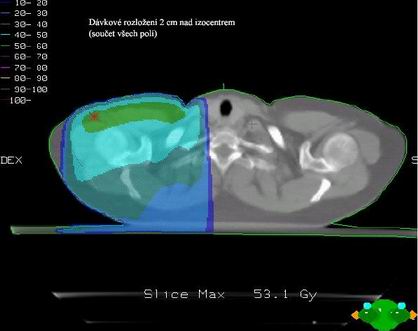

Dvě tangenciální hrudní pole

většinou s klíny

A jedno přímé pole nadklíček + boost axilla Pa pole (8 Gy)

Společné izocentrum pro všechna pole